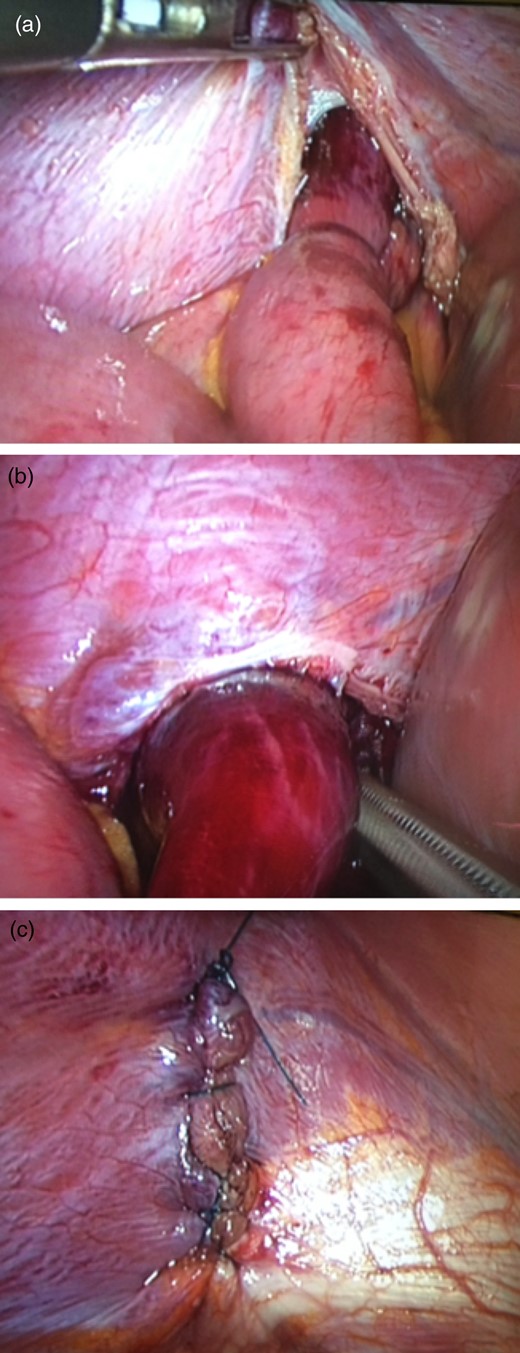

After an initial resuscitation she underwent laparoscopic repair of a diaphragmatic hernia and resection of strangulated jejunum. At laparoscopy, there was a large 5 × 5 cm defect noted posterolaterally on the right hemidiaphragm. To reduce the herniated small bowel, the defect first had to be enlarged with diathermy. Careful bowel handling was necessary to avoid bowel perforation and prevent pleural and peritoneal contamination. The defect was then primarily closed with 0 PDS continuous suture, the small bowel resection was then performed through a protected mini-laparotomy (see Fig. 2).

Laparoscopic images of diaphragmatic hernia repair. Images demonstrate (a) right hemidiaphragmatic defect containing a loop of small bowel the distal end of which is ischaemic, (b) extraction of the bowel loop from the diaphragmatic defect and (c) laparoscopic repair of the defect with 0 PDS.